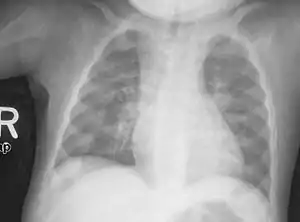

| Rachitic rosary on chest radiograph |

The prominent knobs of bone at the costochondral joints of rickets patients are known as a rachitic rosary or beading of the ribs. The knobs create the appearance of large beads under the skin of the rib cage, hence the name by analogy with the beads of a Catholic Christian rosary.[1]

Rachitic rosary is due to a deficiency of calcium resulting in lack of mineralization and an overgrowth of costochondral joint cartilage. The calcium deficiency may be caused by rickets or other causes of calcium deficiency such as hypoparathyroidism.